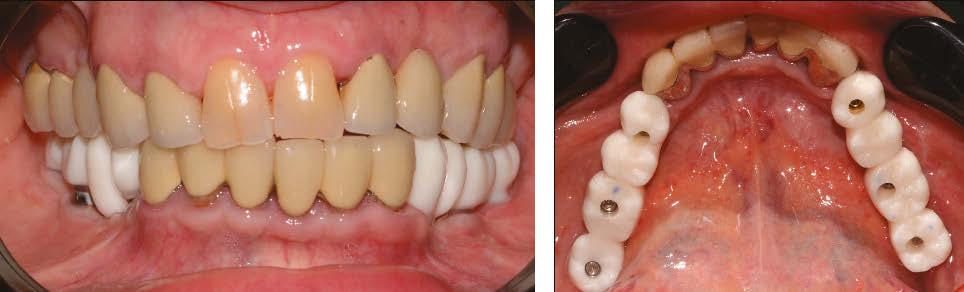

Figure 6 (left): Preoperative situation, panoramic radiograph and intraoral photo. Figure 7 (right): Incisions and flap detachment

Figure 5: Ideal insertion axis for Panthera implants created on the 3D model